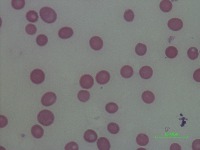

Medical Diagnosis and Research: The "New-Chula" model could be used in medical laboratories and hospitals to automatically identify and classify different cell types in blood samples. This could assist in diagnosing various blood disorders or diseases such as anemia or leukemia, thereby speeding up analysis and treatment processes.

Education and Training: The model could serve as an educational tool for medical students or professionals in training. By using this model, they could learn to identify various types of cells more quickly and accurately, enhancing their understanding of hematology.

Pharmaceutical Trials: During drug testing and development, pharmaceutical companies may use this model to analyze the impact of drugs on different cell types in order to assess effectiveness or side effects.

Public Health Monitoring: Governments and public health organizations could use it to monitor the health condition of the general population, potentially detecting the early stages of an outbreak or epidemic.

Biotechnology Industry: Biotech firms or research labs may use this model for particular research projects involving genetic modification or cellular biology studies where identification and classification of different cell types is necessary.